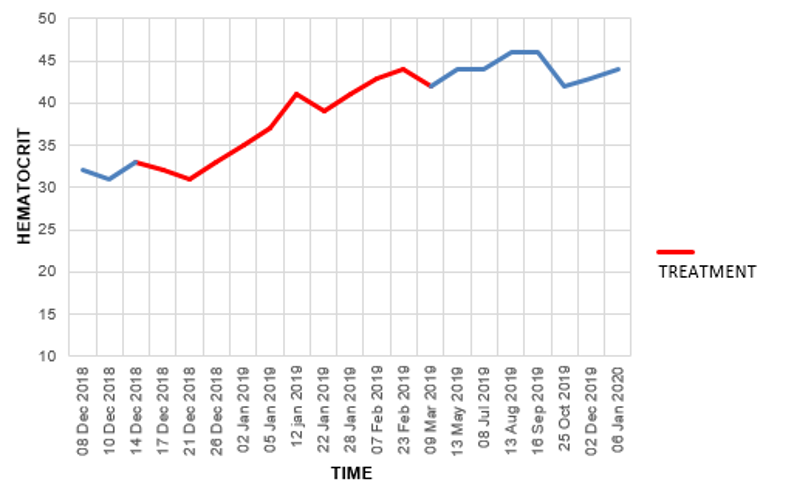

project involved treating approximately 85 patients, with the cure rate

but it is not perfect and will not work for everyone. •Leukemias (particularly acute leukemia) Note: myeloproliferative neoplasms (e.g., polycythemia vera, essential thrombocythemia and primary myelofibrosis) depend upon a mutant protein for survival which was shown to be susceptible to disruption by a few small compounds including hematoxylin. While D-hematoxylin has not been tested on these disorders, this study (along with the other known effects of DMSO and D-hematoxylin) suggest it could be an effective treatment for them. The cancers with a poorer response included: •“Solid” tumors Additionally, if there is a cancer marker associated with the tumor (e.g., CEA or PSA), it will often rapidly drop, making it very easy to track the progress of D-hematoxylin. As the following cases show, many of the improvements were quite profound: •A 54-year-old female patient with Classic Hodgkin Lymphoma which had invaded 72% of her bone marrow, with CD20-positive expression. She had a variety of symptoms (e.g., recurrent pleural effusions and anemia), but since her religion did not permit blood transfusions, she received only D-hematoxylin and EDTA and then had a full recovery (with no recurrence in twelve years of follow up). The most striking aspect of this case was the change in her bone marrow biopsy, after three months of treatment with D-hematoxylin (unlike chemotherapy) it selectively destroyed the cancerous cells, allowing normal ones to regrow and rapidly addressed her anemia. •A 72 year old patient with leukemia who was anemic and had her anemia rapidly improve following D-hematoxylin: Likewise, similar bone marrow changes were seen in her. Note: another similar leukemic patient on D-hematoxylin with anemia had no improvement. After investigating, it was determined this was due to her regularly using WD40 on a daily basis (without respiratory protection) and hence having a bone marrow intoxication which was directly damaging the bone marrow (and in turn the leukemia diagnosis may have been incorrect). •A 16 year old male with a mediastinal seminoma that received 16 D-hematoxylin infusions, 5 IV vitamin C infusions and then one chemotherapy session (on July 7) where cisplatin and bleomycin were combined with DMSO (after which he continued chemotherapy and has recovered from the cancer). •A 63-year-old male with cholangiocarcinoma (a rare, aggressive and notoriously difficult to treat cancer of the bile duct) who received D-hematoxylin plus chelation and vitamin C (but no chemotherapy). During his successful treatment, a drain from his bile duct was also monitored for tumor markers. Additionally, the cancer debris could be seen in the drainage tube (an internal-external percutaneous transhepatic biliary drainage catheter)—something which the Ecuador doctors now view as essential to have if D-hematoxylin will be used in this cancer: Note: another bile duct cancer patient (a 68 year old female) received palliative D-hematoxylin while waiting for surgery and chemotherapy (which ultimately could not be done because of how advanced the cancer was). Her cancer markers levels significantly improved following D-hematoxylin (and continued to reduce during gaps in treatment), but she eventually lost the will to live and passed after 16 months. •A 63-year-old man with B-cell lymphoproliferative disorder who received D-hematoxylin for 10 days (with no other treatment), experienced a significant drop (normalization) of his white blood cell count during that time then stopped at the advice of his hematologists, and two years later died from COVID. •A man who had a stable bladder polyp which became cancerous following a covid vaccination (with the initial sign being a large blood clot in the urine) which when examined had spread in a large portion of the urinary tract’s endothelium. It was surgically removed, but due to how far it had spread, the urologist told the patient he would only survive for two months. They then began five weeks of intravesical and IV D-hematoxylin, and in four years, the cancer never returned (which led to the urologist telling everyone about the “amazing” surgical procedure they had performed). •A 55-year-old female who had a mediastinal tumor (type unknown as it was wrapped 560° around the aorta and hence could not be biopsied) which fully resolved after 33 daily D-hematoxylin treatments. Additionally, this was the CT prior to treatment where the tumor can be seen around the aorta: While this was the CT two weeks following the D-hematoxylin treatment: Lastly, at five years follow up, there was no recurrence. •A 27-year-old female with acute lymphoblastic leukemia reacted poorly to two sessions of chemo, was classified as terminal, and then was started on D-hematoxylin. She had a significant improvement in her cancer and simultaneous improvement in her anemia which continued long after conventional treatments for anemia were halted (which did not include blood transfusions as she was a Jehovah’s Witness). In a before (1-2-2020) and after (2-1-2020) video I saw of this patient, she initially looked very frail and had difficulty walking, while just a month later (after 31 days of treatment), she had no difficulty walking and looked vibrant and robust. Additionally, they continued to monitor her on a monthly basis, and four years later, she’d had a healthy baby, and had her hematocrit range from 42 to 48 (which is slightly above average) indicating she had no further risk of anemia (even though hematologists in the hospital had predicted her reckless pregnancy would cause severe anemia). Additionally, her ESR (which had been significantly elevated prior to treatment) normalized (and remains normal 5 years later). Lessons from EcuadorIn addition to observing a remarkable degree of success from D-hematoxylin, the Ecuadorian team was able to discern a variety of patterns (many of which mirrored Tucker’s previous observations) that helped craft their treatment protocols. For example: •While DMSO alone can somewhat help with cancer, the effects of DMSO combined with hematoxylin are completely different from what would be observed with DMSO alone. •They saw many signs during their treatment protocols that D-hematoxylin selectively targeted cancer cells. •Cancers did not develop resistance to D-hematoxylin (which is a common challenge with many chemotherapies). •While some tumors rapidly disappear, other types frequently become avascular (which stops their growth) and dried-out, blanched, or fibrous rather than being directly shrunk (e.g., I reviewed cases where a brain cancer simply stopped growing). In many cases, those tumors are then very easy to extract surgically. Note: to my knowledge, everyone besides that Ecuadorian team who treats with D-hematoxylin still uses Tucker’s protocol and has not tried to improve upon it. Variations in D-Hematoxylin EfficacyOn